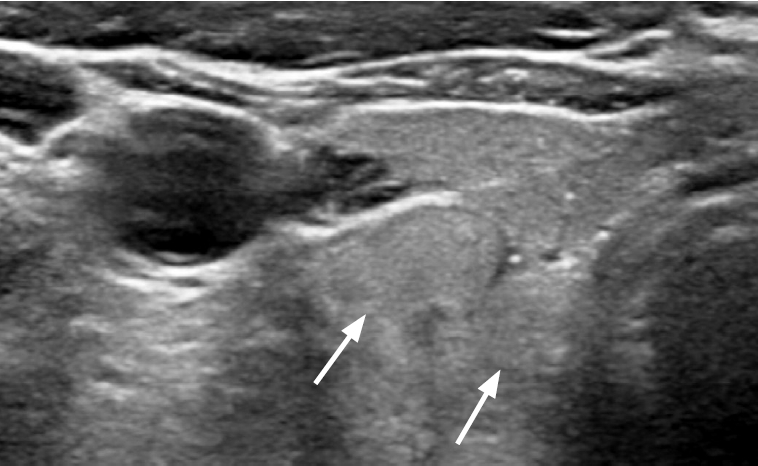

Fig. 3.

Normal parathyroid gland with typical ultrasound features in the infrathyroid paramedian central neck in a 41-year-old female patient (case 5).

A, B. Transverse and longitudinal images show an ovoid, homogeneous, markedly hyperechoic parathyroid gland in the left infrathyroid central neck (arrows).